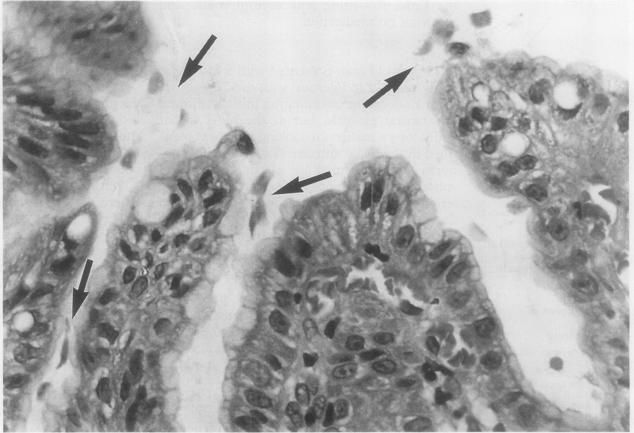

Two cases of chronic giardiasis of the stomach diagnosed from gastric mucosal biopsy specimens are reported. The first case was associated with an acute-on-chronic gastritis and Helicobacter-like organisms, and the second with an adenocarcinoma of the stomach. In both cases the trophozoites had been missed in earlier biopsy specimens. As far as is known this is the first report of giardiasis of the stomach.

报告了两例经胃黏膜活检标本诊断为慢性胃贾第虫病的病例。第一例与慢性活动性胃炎及类幽门螺杆菌有关,第二例与胃癌有关。在这两例中,早期活检标本均未发现滋养体。据所知,这是胃贾第虫病的首例报告。